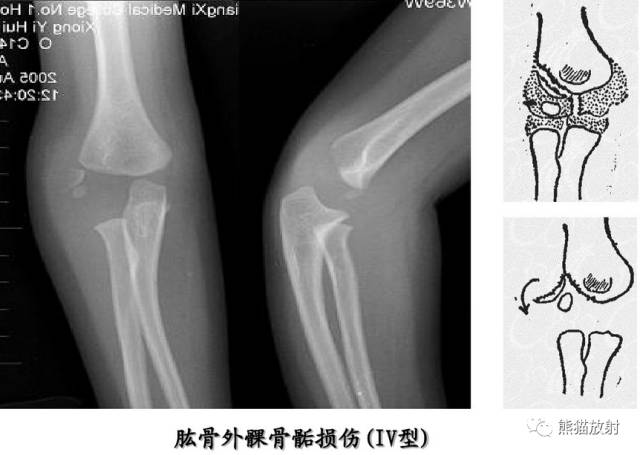

Salter-Harris IV型:骨折累及骺板、干骺端及骨骺,属于关节内骨折。

第四型(Ⅳ型) 骨骺和干骺端骨折。该型也较多见,仅次于第二型,占30.2%;骨折线呈斜形贯穿骨骺、骺板及干骺端,由于骨折线同过生长板全层,所以容易引起生长发育障碍和关节畸形,多见者为鱼尾状畸形。此型多见于10岁以下小儿的肱骨外髁及年龄较大儿童的胫骨远端,此型必须切开复位及内固定。